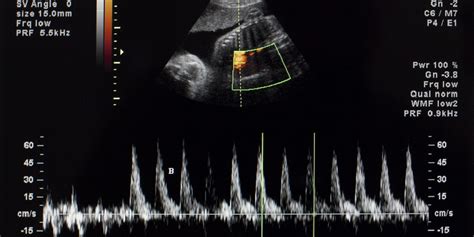

Flussimetria Doppler: Studio dell'Emodinamica

La flussimetria è la determinazione del flusso del sangue in un vaso. La tecnica flussimetrica Doppler è una metodica utile per lo studio dell'emodinamica fetale, feto-placentare ed utero-placentare. Alterazioni dell'emodinamica in questi distretti possono essere in grado di mettere in evidenza una sofferenza fetale cronica. Con la flussimetria si valuta il rapporto fra sistole e diastole e sono stati proposti vari indici, che dovrebbero rispecchiare il grado di distensibilità del vaso e quindi dare un'idea delle resistenze periferiche. Questi indici vanno a diminuire con il passare delle settimane, mentre si mantengono abbastanza costanti nell'aorta. Esistono due tipi di apparecchi: il "Doppler continuo" ed il "Doppler pulsato". Un meccanismo fondamentale di difesa del feto in situazioni di ipossia è la cosiddetta "centralizzazione del circolo", cioè la riduzione del circolo nel distretto corporeo "meno nobile" nel tentativo di mantenere un circolo più o meno normale a livello cardiaco e cerebrale. In caso di sofferenza fetale, si deve ricercare questo segno tramite la flussimetria, che evidenzia la riduzione del circolo nell'aorta discendente.